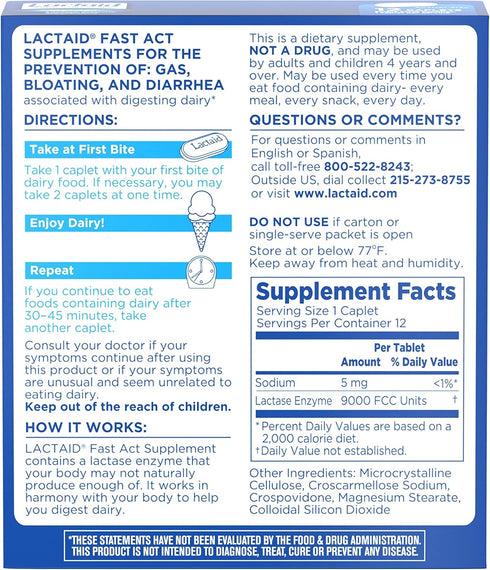

Formulated with 9000 FCC lactase units of natural lactase enzymes, the caplets break down milk sugar to reduce discomfort from dairy sensitivity due to lactose

The easy-to-swallow dairy digestive aid is certified Kosher and is suitable for both adults and children, ages 4 and up

The fast-acting formula of the lactase pills starts working with your first bite or sip of dairy; if you continue to eat foods containing dairy after 30-45 minutes, take another caplet for continued relief